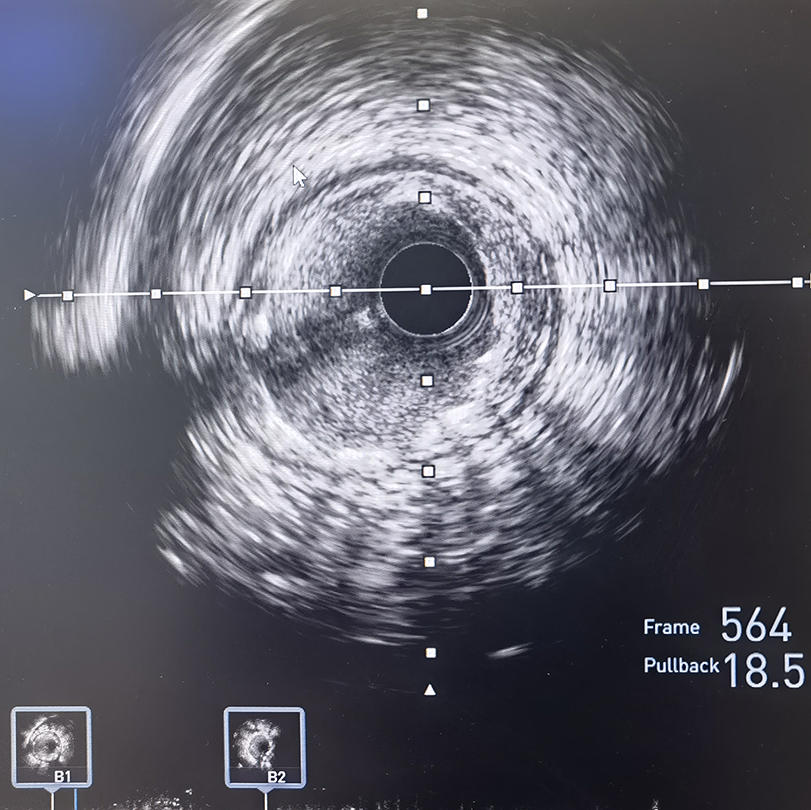

冠脉造影及IVUS检查提示前降支重度狭窄伴严重钙化